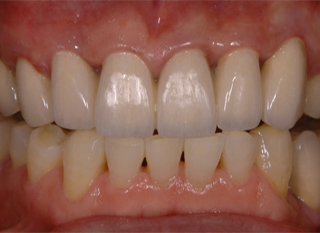

写真は、歯並びの不整とアンバランスな歯と歯茎のラインや歯の長さを改善するため、矯正治療の後に不揃いな歯茎を切除し形態を自然な歯の長さに回復した状態です。